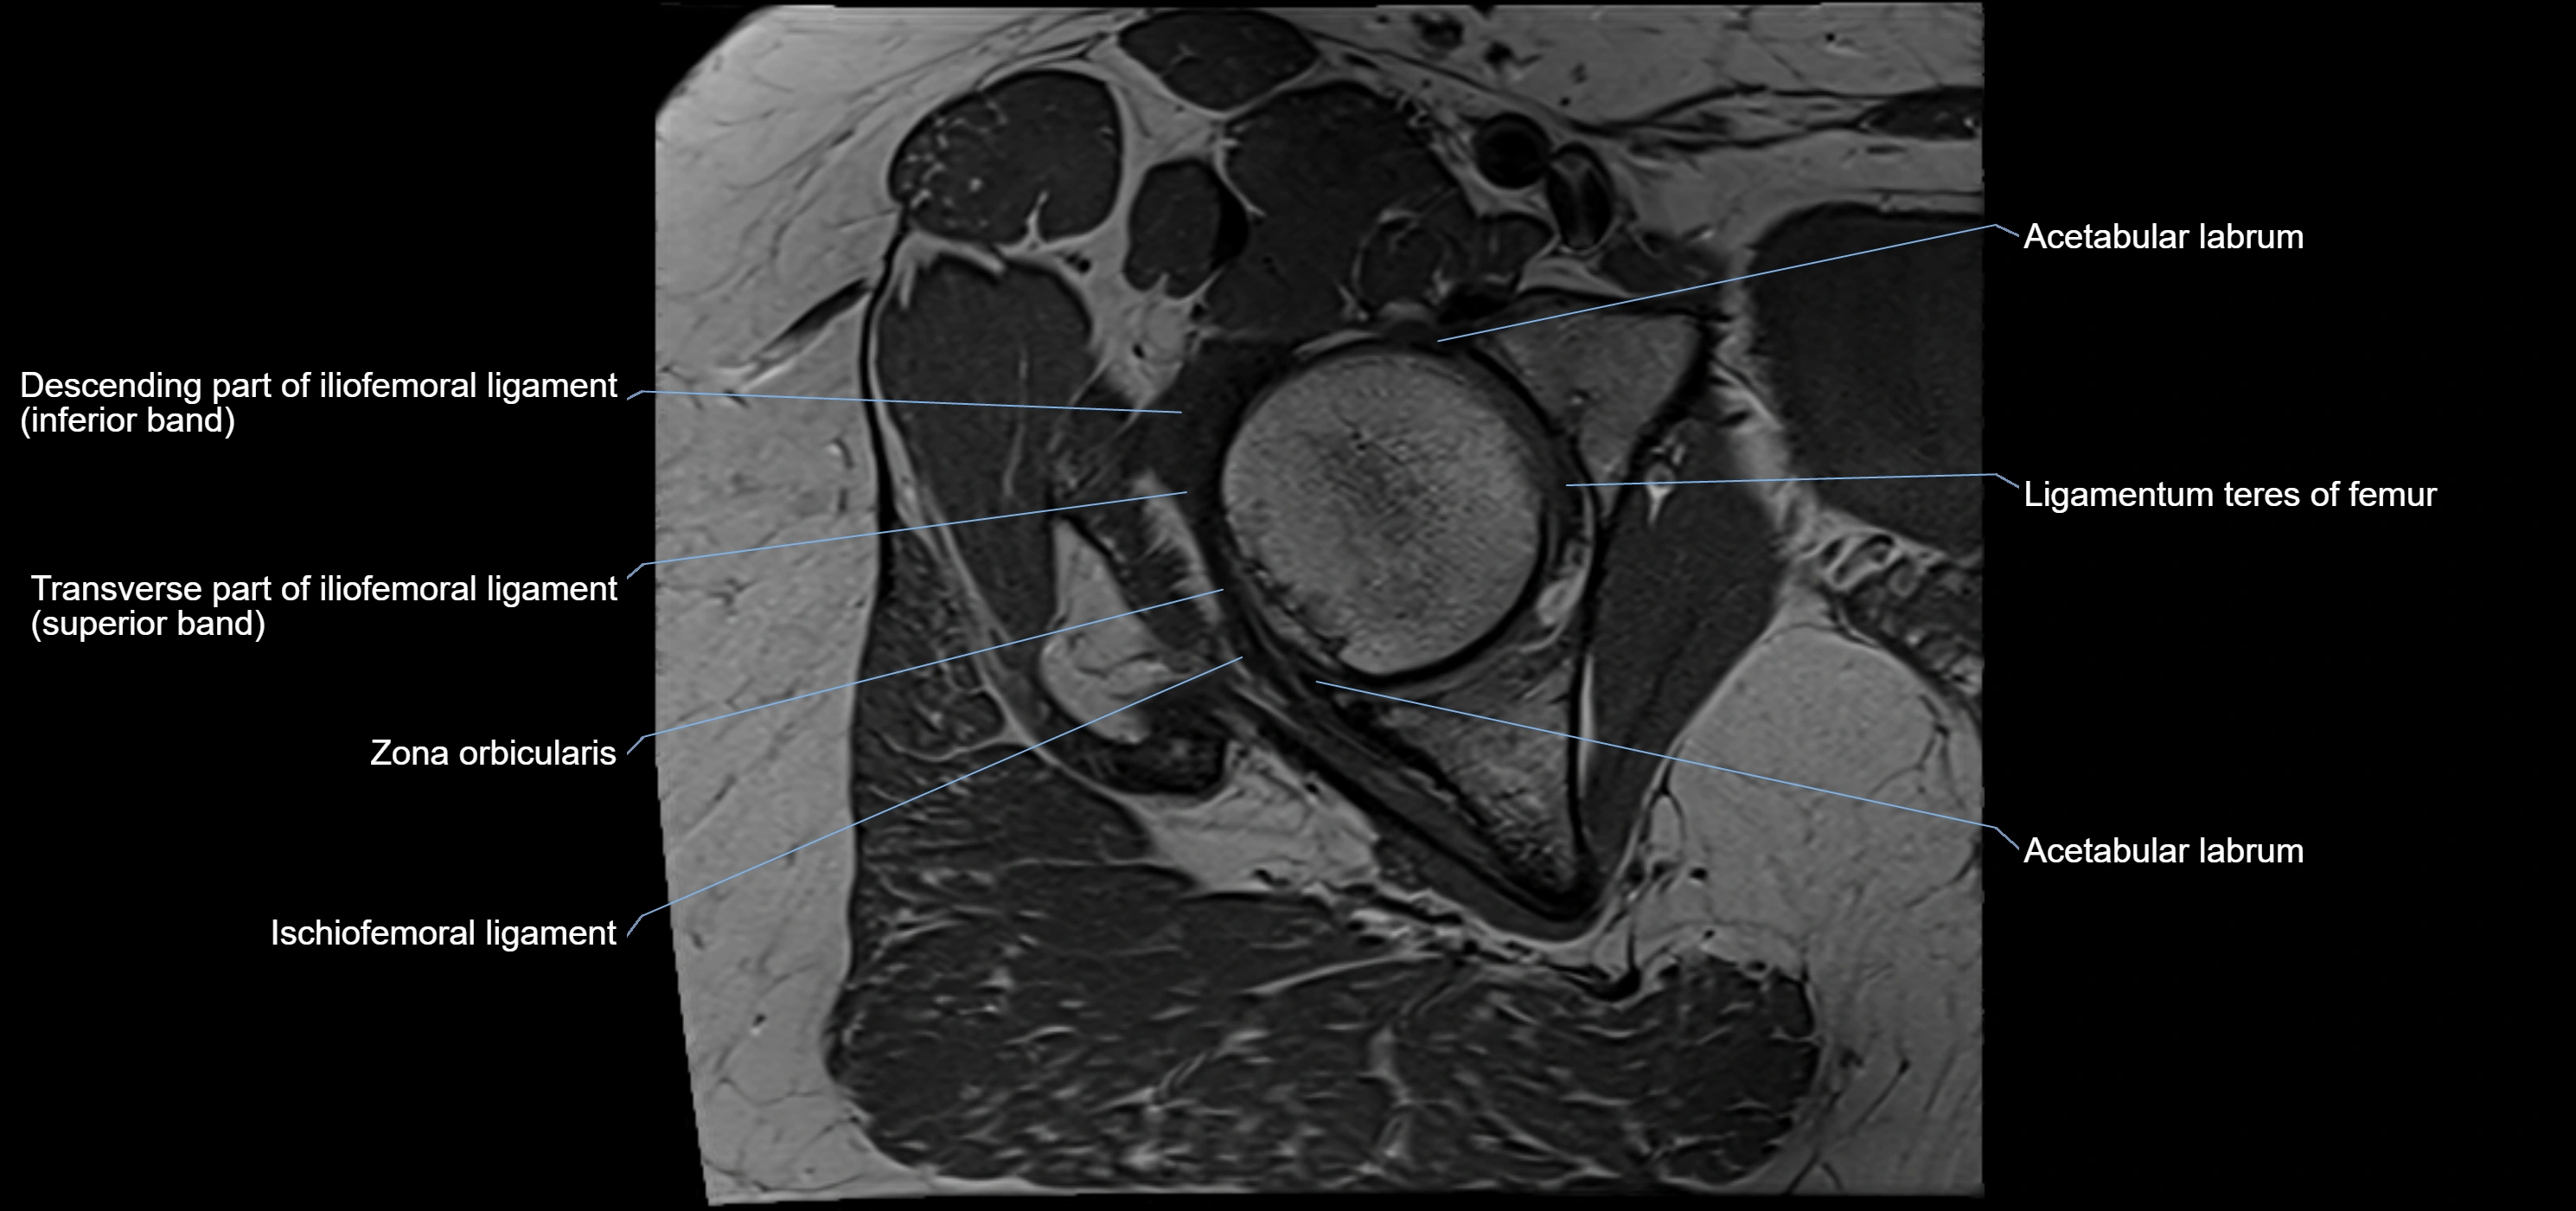

MRI Appearance

T1-weighted images:

• Labrum: low signal intensity (dark)

• Surrounded by intermediate signal joint fluid (bright on arthrogram)

• Tears: linear or focal areas of intermediate-to-high signal interrupting labral continuity

T2-weighted images:

• Joint fluid: bright, making labral tears visible as fluid extending into or around labrum

• Degeneration: may show areas of increased signal within labrum

MRI image

image